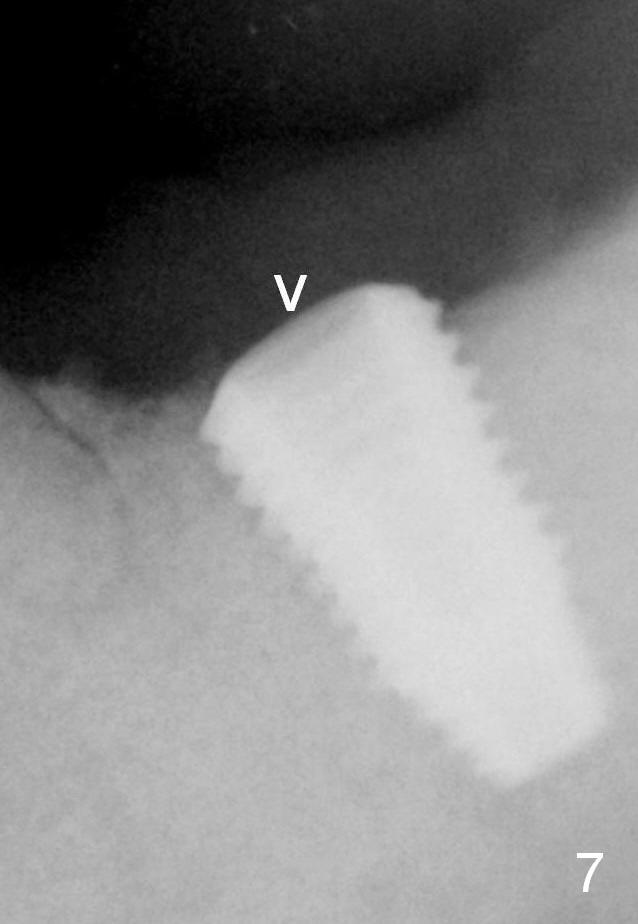

Two months postop, the healing screw is lost (Fig.7 arrowhead), while bone graft retains (Fig.8 *).